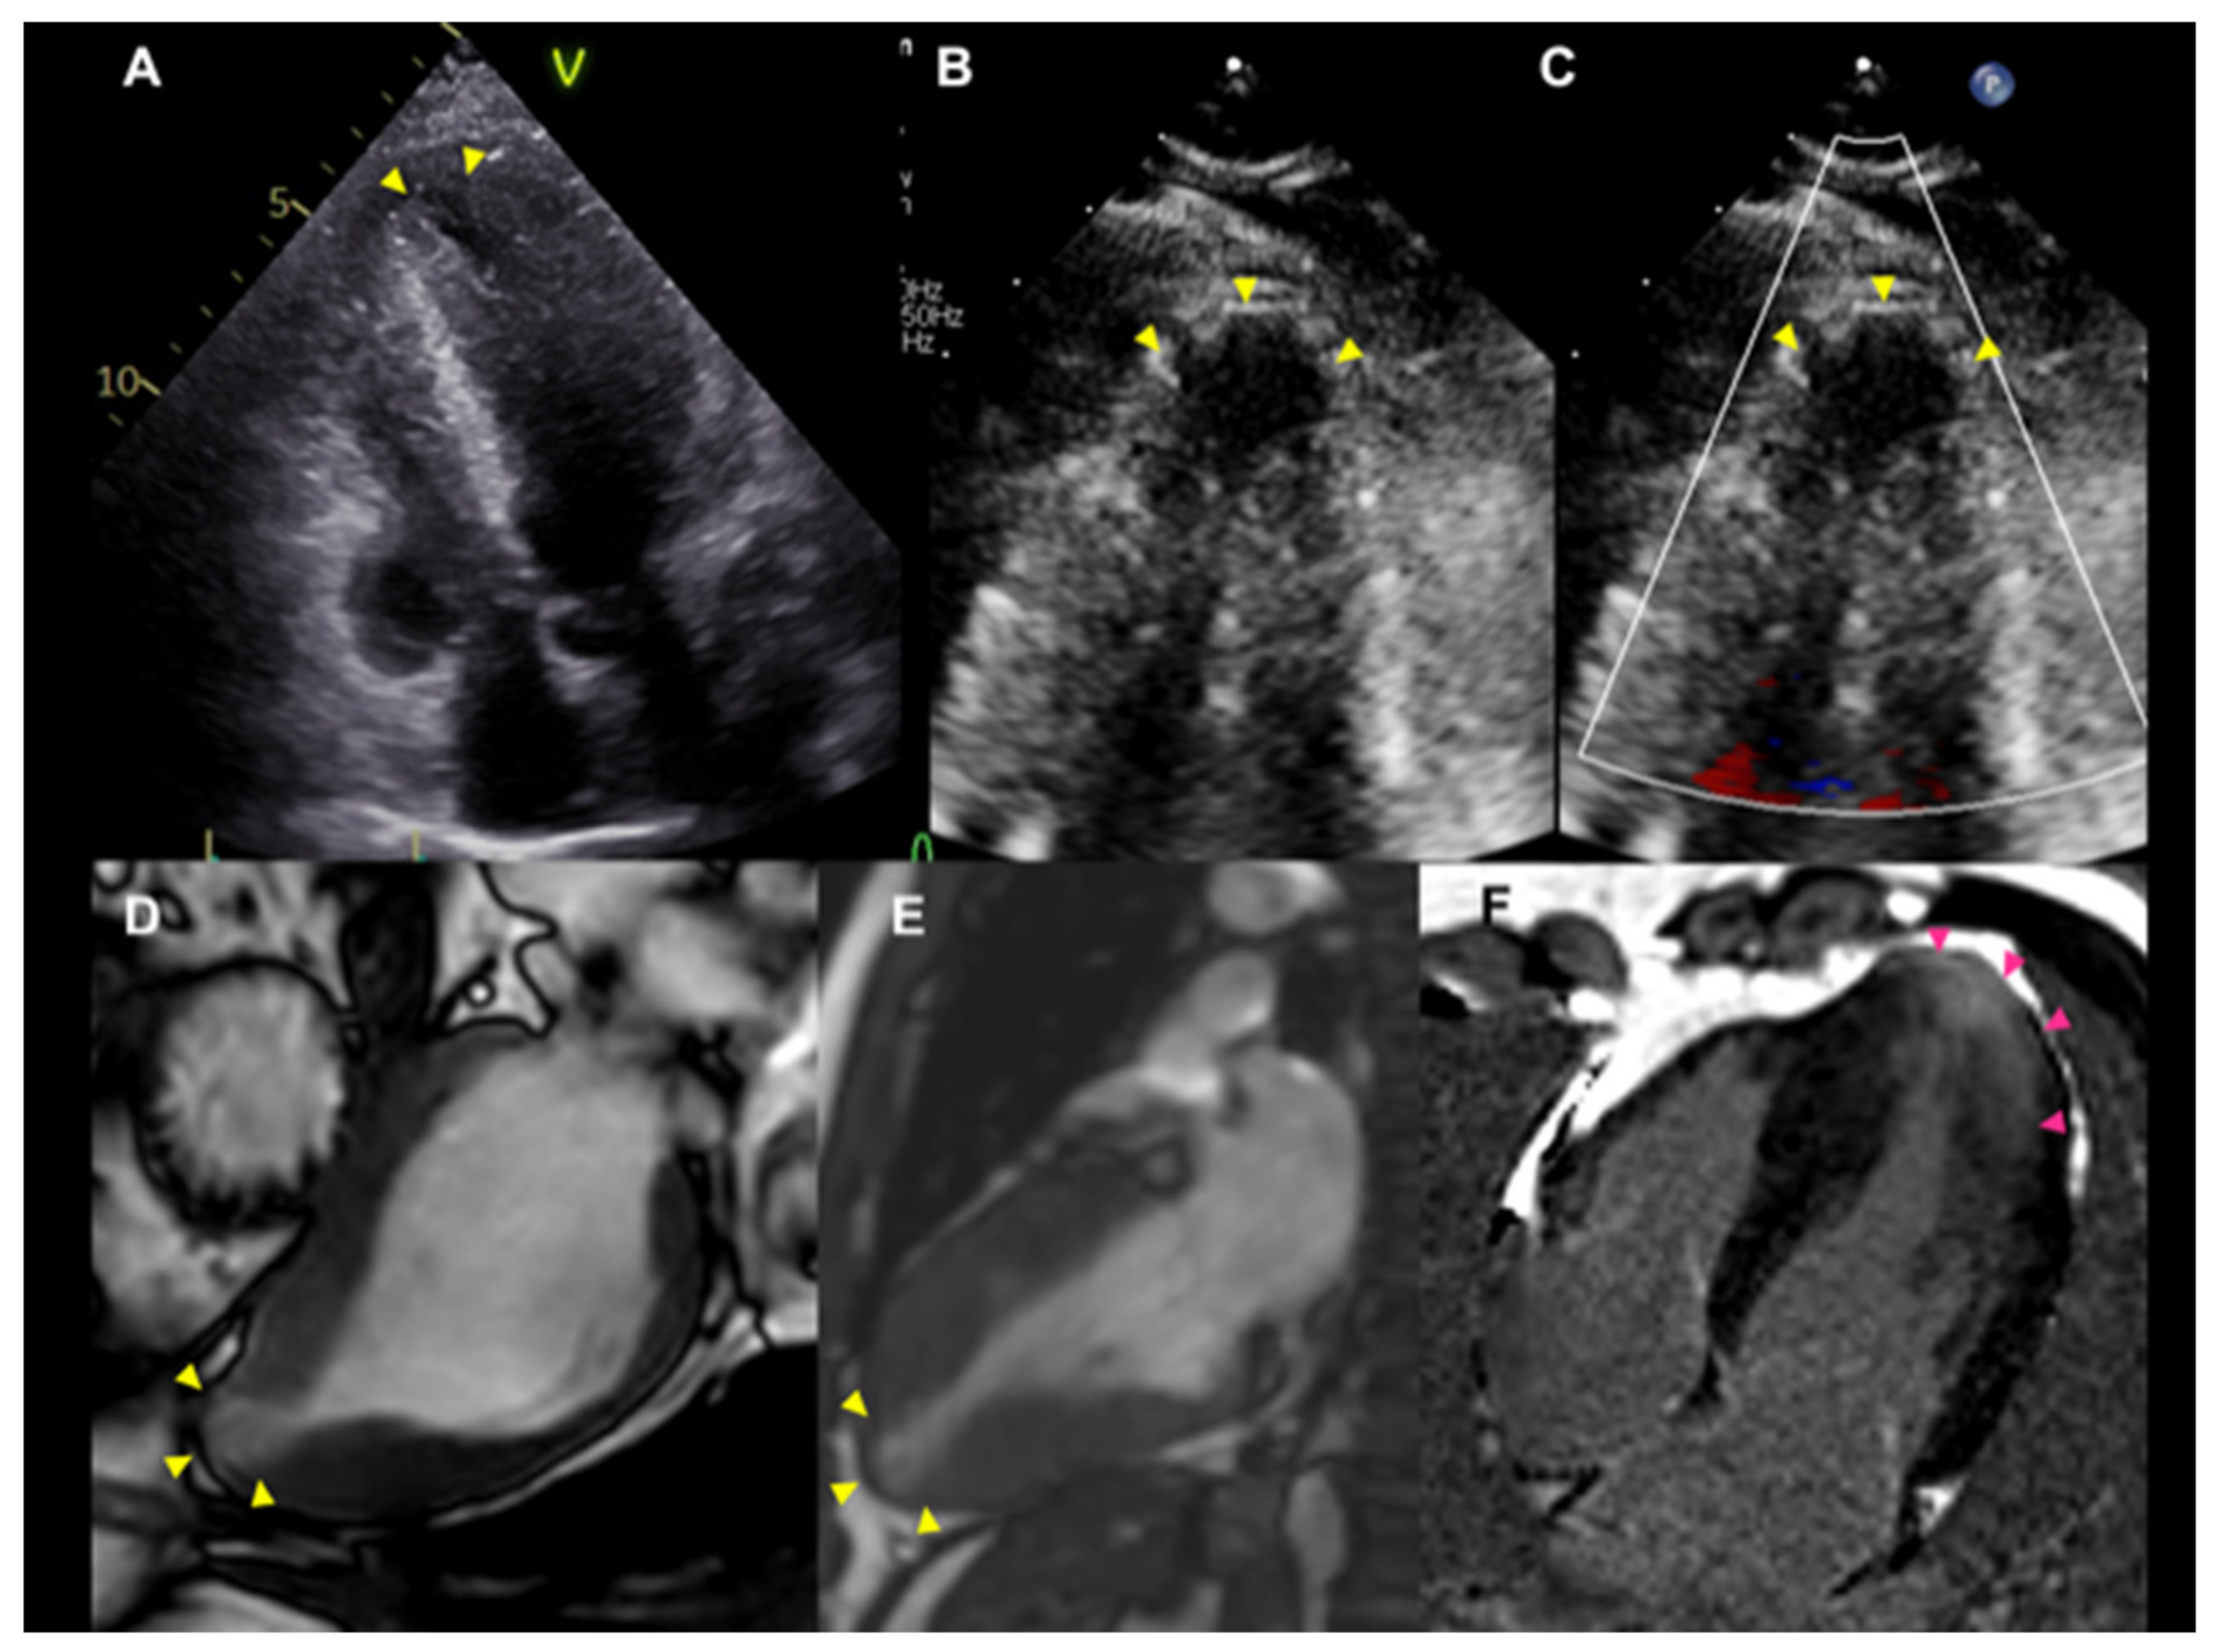

3.3. Mid-Ventricular Obstruction (MVO) and Left Ventricular Apical Aneurysm (LVAA)

3.4. Reduced LV Function (Dilated Phase/End-Stage/Advanced Stage)